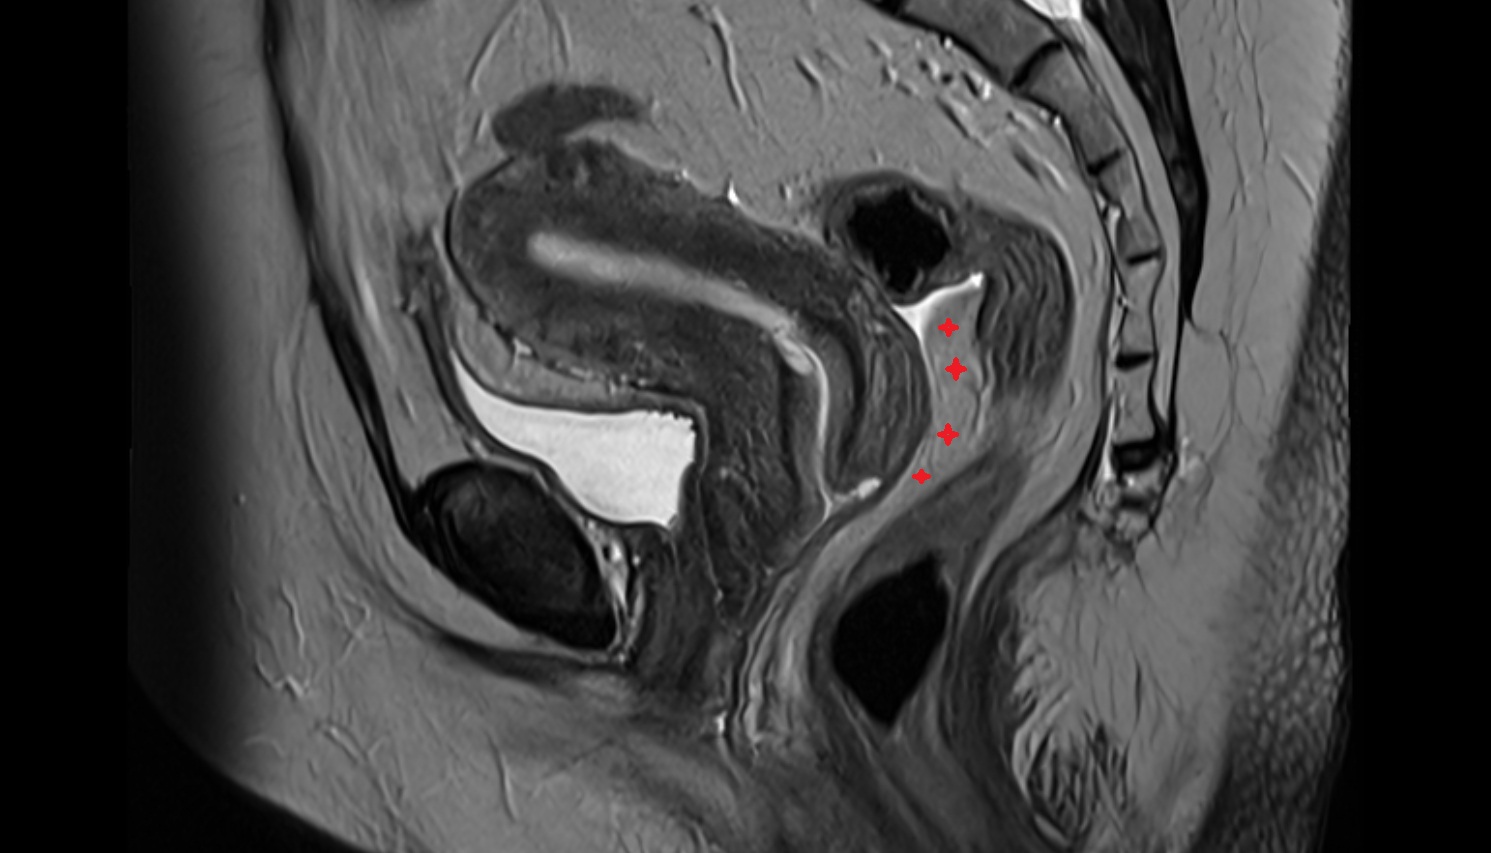

- Uterus

- Body of uterus

- Cervix of uterus

- Isthmus of uterus

- Vagina

- Fornix of the vagina

- Endometrium of uterus

- Myometrium of uterus

- Junctional zone of uterus

- Endocervical canal

- Stroma of the cervix

- Internal os of the cervix

- External os of the cervix

- Vesicouterine pouch

- Rectouterine pouch (pouch of Douglas)